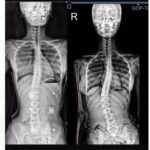

21 Mart 2025’te Bursa Şehir Hastanesi’nde dünyaya gelen Çağan Ata Taran, henüz 18 günlükken SMA Tip-1 hastalığına yakalandığını öğrendi. Şu an hiçbir semptom göstermese de bu sinsi hastalık, kaslarını eritmeden ve onu hayattan koparmadan önce hayati bir mücadele verilmeli.

Anne Aleyna ev hanımı, baba Ahmet Miraç işletme şefi. Ailenin ilk göz ağrısı olan Çağan Ata, yurtdışında sadece özel izinle kullanılabilen ve oldukça pahalı olan Zolgensma ilacına ulaşabilirse bu ölümcül hastalığı yenme şansına sahip olacak.

Gün geçtikçe etkisini artıran bu ölümcül kas hastalığına karşı en etkili tedavi için zaman daralıyor. SMA hastalığında erken tedavi hayati önem taşıyor. Tedavi ne kadar gecikirse, hasar da o kadar kalıcı oluyor.